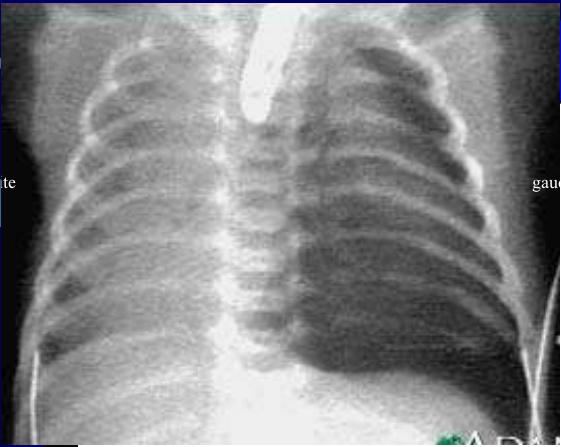

Technique radiologique de choix pour diagnostic

atresie congenitale est transit oesophagien ou

oeso-gastro-duodenale ( TOGD ) .

Diagnostique

prenatale est difficile

:Grossese hydramios ++ , Estomac non vue ( Type I,II ) ,avec

des autres malformations . A salle de

naissance , une cliche de face thoraco-abdominale et

cliche cervico-thoracique de profile avec sonde radio-opaque

butee en oesophage . La trajet du sonde se donne la cite de

atresia ou non ou bien en presente la fistule

tracheo-oesophagienne

Image

radiologique de atresia congenitale de type I . La

contrast arrete a D4 sur la bifurcation de

trachee |

|

Un sonde radio-opaque bute dans oesophage

se donne la cite de atresia . Cliche

thoracoabdominale de face . |